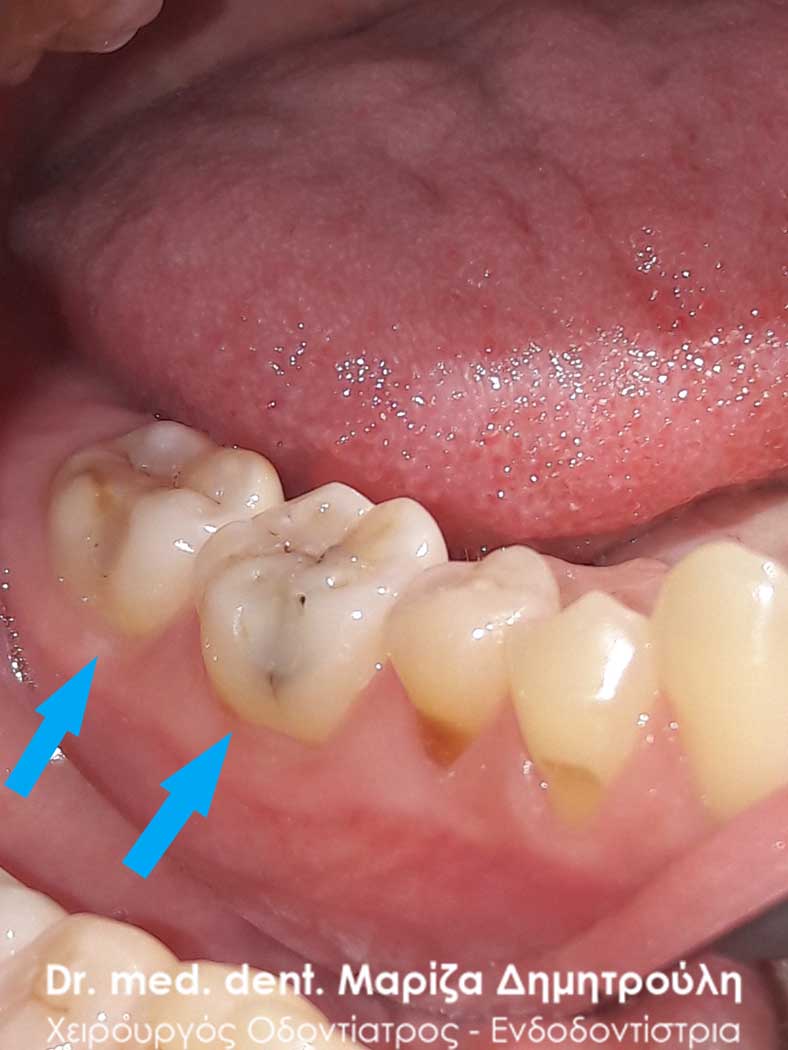

Αρχική εικόνα κάτω αριστερών γομφίων

Η ασθενής αισθανόταν τις τελευταίες μέρες έναν ήπιο πόνο κατά τη μάσηση τροφών. Μετά την κλινική εξέταση του στόματος διαπιστώθηκε η ύπαρξη τερηδονικών κοιλοτήτων στους δύο άνω αριστερούς γομφίους. Αποφασίστηκε με τη συναίνεση της ασθενούς η αντικατάσταση των σφραγισμάτων. Στον πρώτο γομφίο διορθώθηκε μόνο η μισή έκταση του παλιού σφραγίσματος, καθώς κρίθηκε οτι δεν ήταν απαραίτητη η αφαίρεση ολόκληρου του παλιού σφραγίσματος.